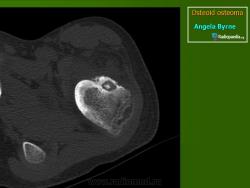

При рентгенологическом исследовании остеоид-остеома обнаруживается как субкортикально расположенный участок окостенения, окруженный ободком остеосклероза, ширина которого увеличивается по мере прогрессирования опухоли. При этом центральная часть опухоли становится менее заметно. Граница между центральной светлой зоной и склеротическим ободком, отчетливая в ранний период, со временем стирается вследствие того, что центральная зона опухоли подвергается оссификации и обызвествлению, которые распространяются центробежно. Рост кортикальных и субпериостальных остеоид-остеом сопровождается также реактивным склерозом- Имеются указания и на то, что если новообразование растет в костномозговом канале, то в соответствующей кости развивается остеопороз. Обычно опухоль легко вылущивается из окружающей кости и макроскопически представляет собой мелкозернистую, красновато-бурую костную ткань. Остеоидную остеому, как правило, удаляют хирургическим путем. Рецидив возможен, но практически не встречаются. Если он и происходит, то спустя 10 лет и позднее после удаления первичного узла опухоли.

Рентгенологическая картина. На обзорных рентгенограммах очаг поражения характеризуется утолщением и уплотнением кортикального слоя кости вокруг небольшого литического гнезда.

Osteoid osteoma: intracortical